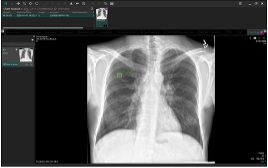

EIRL Chest Screening |

・EIRL Chest Screening